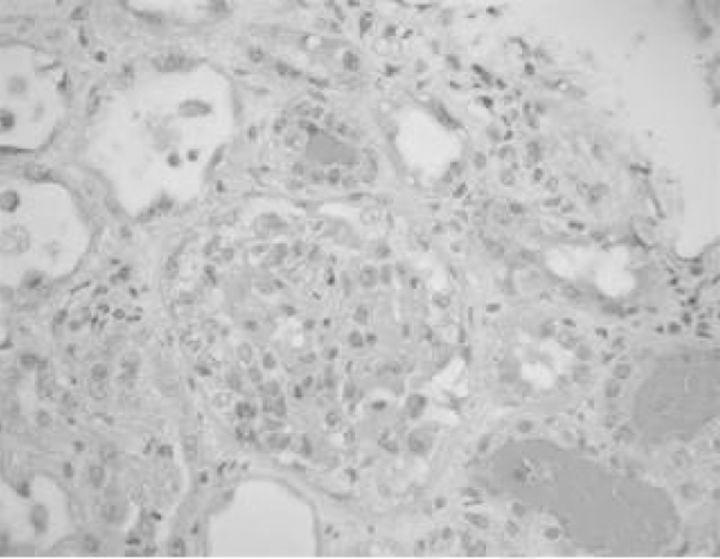

单剂量奎宁引发的肾局限性血栓性微血管病和急性间质性肾炎。

Renal-limited thrombotic microangiopathy and acute interstitial nephritis with a single dose of quinine.

Quinine has been reported to cause acute kidney injury by various mechanisms. The response to quinine can result in a spectrum of problems ranging from isolated thrombocytopenia to thrombotic microangiopathy (TMA) to disseminated intravascular coagulation. Quinine has also been reported to cause acute interstitial nephritis (AIN). We report an unusual presentation where both of these entities of renal-limited TMA and AIN were precipitated by a single dose of quinine.

摘要

据报道,奎宁可通过多种机制导致急性肾损伤。对奎宁的反应可能会引发一系列问题,从孤立性血小板减少到血栓性微血管病(TMA),再到弥散性血管内凝血。也有报道称奎宁可导致急性间质性肾炎(AIN)。我们报告了一例罕见病例,单次服用奎宁引发了局限于肾脏的TMA和AIN这两种情况。